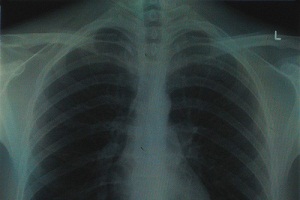

Amianto, perché è così pericoloso per la salute? In linea di massima la grande pericolosità dei manufatti contenenti amianto risiede nella possibilità che questi liberino le famigerate fibre, che possono essere inalate. In tal caso, parte di queste anziché essere inalate restano nei polmoni per tutta la vita.